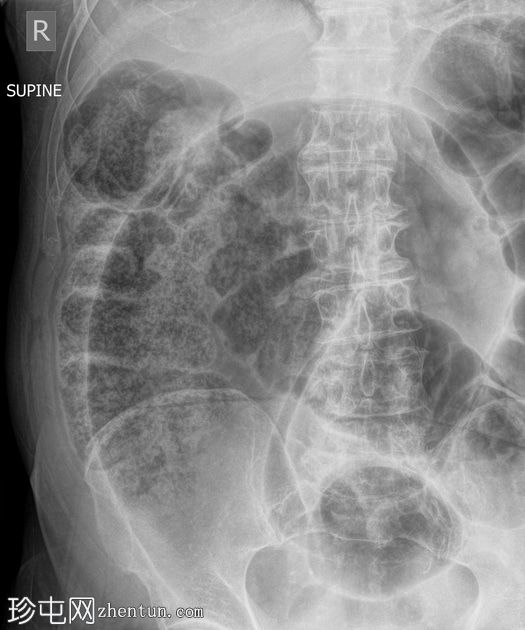

正位片

大肠袢扩张,呈“咖啡豆征”,直肠内未见气体,提示乙状结肠扭转。